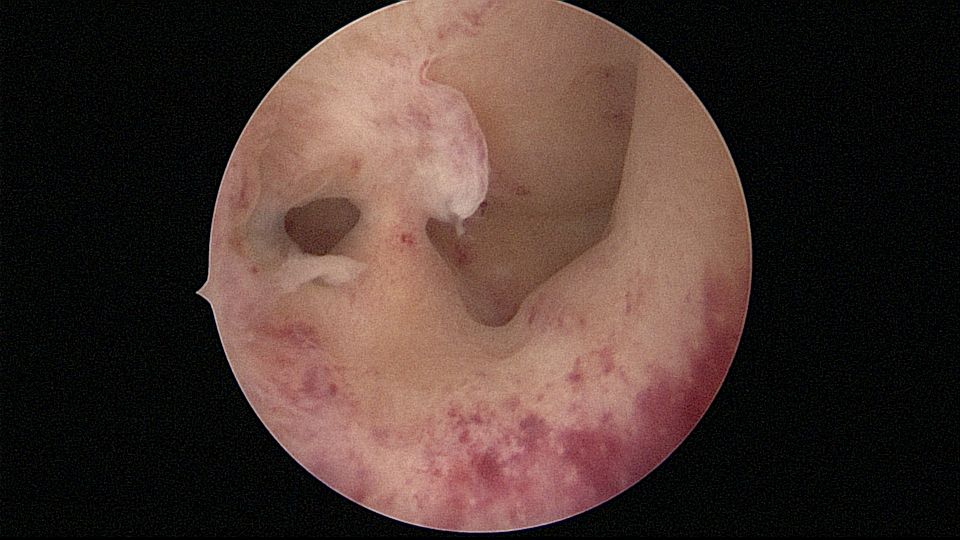

患者28岁,G1P0,2019年11月孕9周胎停1次,药流清宫,术后月经量逐渐减少,淋漓不净。外院B超发现宫腔粘连,2021年6月初宫腔镜探查,宫腔两侧及右侧宫角粘连,单级电针分粘,恢复宫腔形态,显露双侧输卵管开口(术中图像采集系统突发故障,分粘及分粘后图片未采集到)。2021年6月底宫腔镜二探取球囊,宫腔形态正常,双侧输卵管开口可见。2022年12月自然妊娠,足月顺产。现33岁,G2P1。